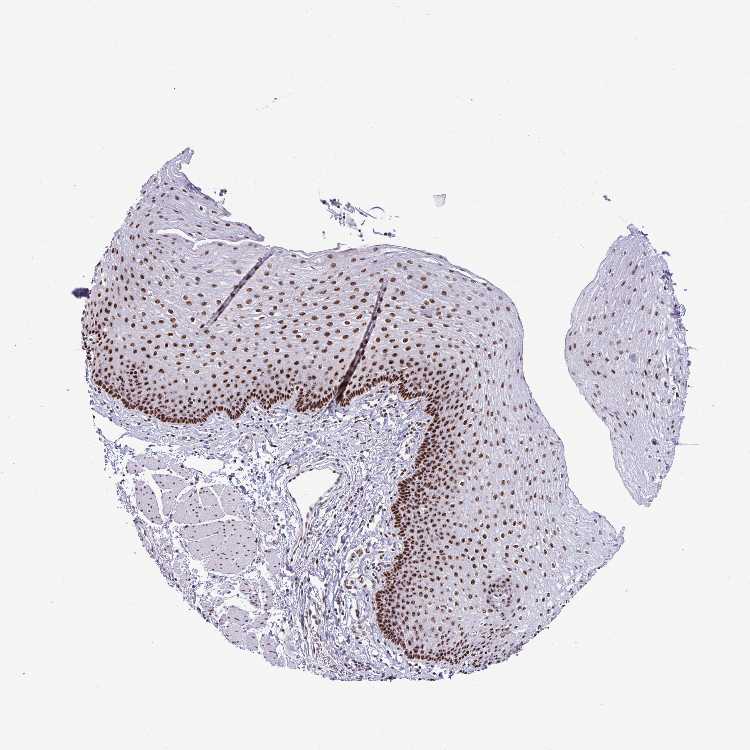

ESOPHAGUS - Antibody stainingi

Antibody staining in the annotated cell types in the current human tissue is reported as not detected, low, medium, or high, based on conventional immunohistochemistry profiling in selected tissues. This score is based on the combination of the staining intensity and fraction of stained cells.

Each image is clickable and will lead to virtual microscopy that enables deeper exploration of all samples and also displays staining intensity scores, fraction scores and subcellular localization as well as patient and tissue information for each sample.

Antibody HPA060760

Squamous epithelial cells High